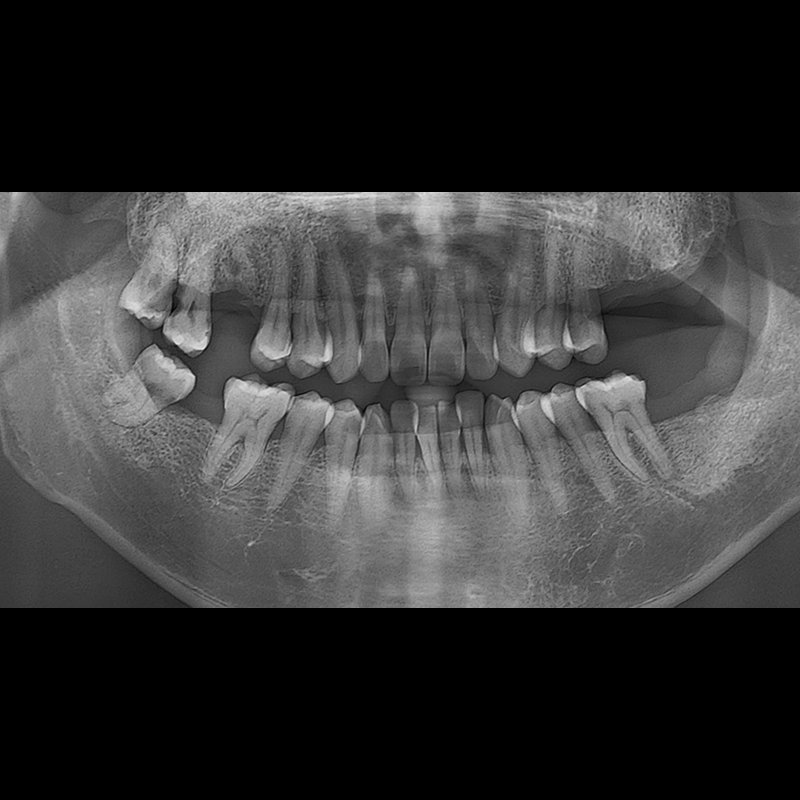

种植牙前后的照片 2025.05.30

在缺失的牙齿部分和难以挽救的牙齿位置植入了种植牙。